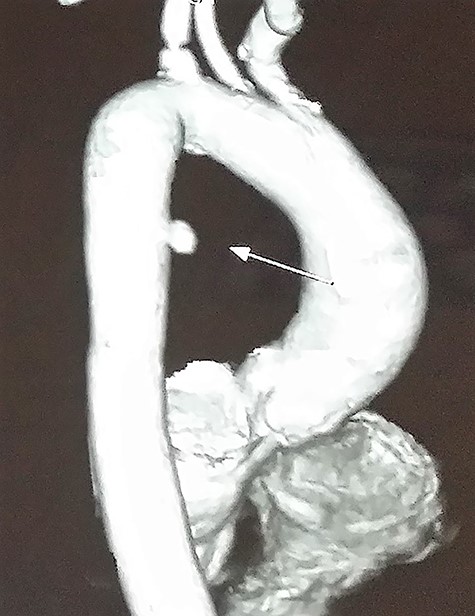

Contrast-enhanced chest computed tomography (CE-CT) with thoracic and abdominal aortogram showed a saccular aneurysm arising from the right lateral wall of the proximal descending thoracic aorta (10 × 8 mm, neck 8 mm) with peri-aneurysmal hematoma tracking along the left posterior mediastinum, causing anterior displacement of the esophagus and a left-sided hemothorax suggestive of a ruptured aneurysm (Figs 2 and 3).

CE-CT image showing saccular aneurysm arising from the proximal descending thoracic aorta.